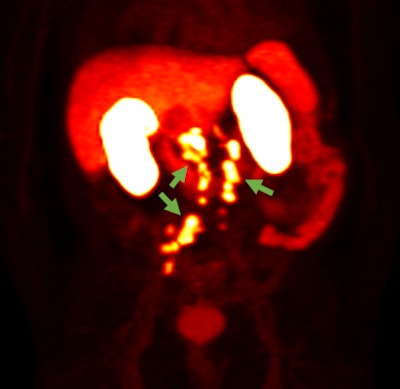

F-18 rhPSMA-7.3 PET image showing prostate cancer spread beyond the prostate region. Photo courtesy of Blue Earth Diagnostics.Blue Earth submitted the NDA for the use of F-18 rhPSMA-7.3 in PET imaging of prostate cancer, according to the vendor. The submission was supported by clinical data from one prospective phase I study and two prospective phase III clinical trials, Blue Earth said.